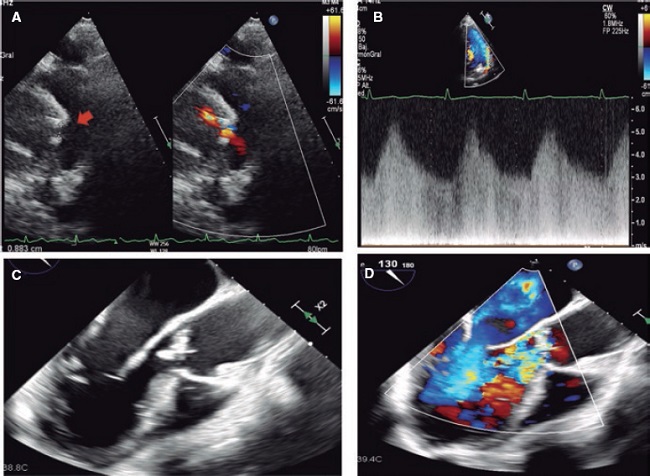

Mujer de 52 años que ingresó por ictus isquémico tratado con trombectomía mecánica. Refería fiebre durante el mes previo y en la exploración destacaba un soplo continuo sistólico-diastólico. Se le realizó un ecocardiograma que evidenció ductus arterioso persistente de 7 × 5 mm con repercusión hemodinámica (sobrecarga de cavidades izquierdas) (figura 1A,B, flecha; vídeos 1 y 2 del material https://doi.org/10.24875/RECIC.M23000427adicional). Se detectó además una verruga sobre la válvula aórtica, con ligera insuficiencia. En hemocultivos se aisló Streptococcus sanguinis. La angiografía de tórax por tomografía computarizada, además de caracterizar el ductus, mostró una vegetación sobre el tronco pulmonar con embolias sépticas pulmonares (figura 2A-D, flecha). Se pautó tratamiento antibiótico por 4 semanas. Ante el empeoramiento ecocardiográfico (crecimiento de vegetación y progresión de la insuficiencia) (figura 1C,D; vídeos 3 y 4 del material adicional https://doi.org/10.24875/RECIC.M23000427adicional) se decidió intervenir quirúrgicamente para sustituir la válvula aórtica por una prótesis mecánica y cerrar el ductus con parche.